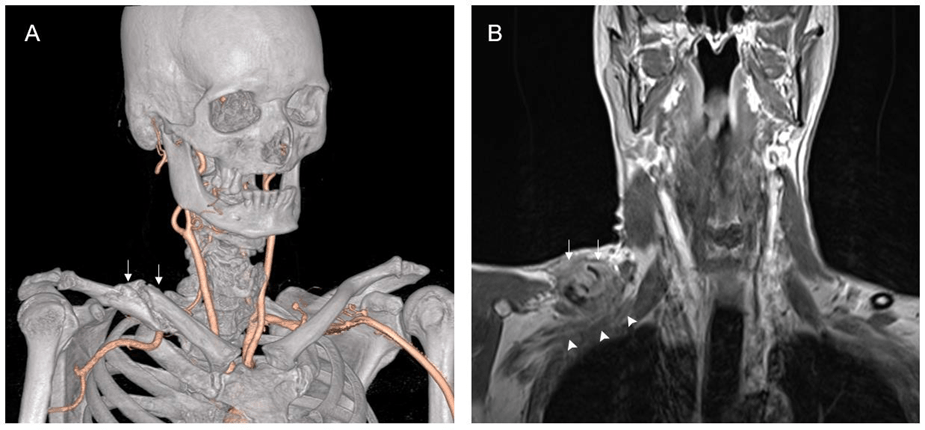

- Thoracic Outlet Syndrome (TOS)

- Compression of nerves or blood vessels in the thoracic outlet, located between the neck and shoulder.

- Symptoms: Shoulder and neck pain, numbness in the arm or hand, and sometimes vascular issues.